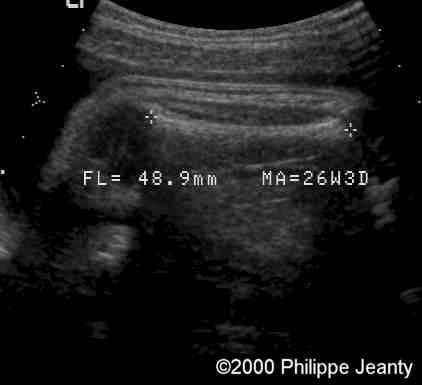

The arm demonstrates too much soft tissue on a too short skeletal frame.

case0020-1

Humerus and femur (below) are too small (see chart below).

case0020-2

The femur (and humerus are way below the 5th percentile).